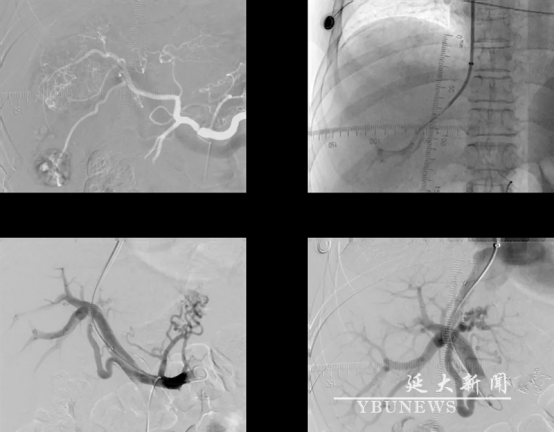

TIPS是“介入手术的珠峰”,被公认为介入领域难度最高、风险最大的四级手术之一,需在肝静脉与门静脉间精准架设“血管立交桥”,穿刺误差需控制在0.5mm内,稍有不慎即可能穿刺大血管,引发大出血。此前,此类手术仅在省外或省会城市才能实施,本次由朴龙镇主任率队全程独立操作,完成延边地区该技术自主攻坚“零的突破”。

该技术集合了多项介入医学的核心技术。术中通过局部麻醉微创穿刺,在肝内植入支架建立分流道,将门静脉高压血流直接引流至下腔静脉。术后降低了门静脉压力,同时术中一并进行胃冠状静脉栓塞治疗,避免再次消化道出血。

手术历时三小时,团队依托术前CT三维重建及术中DSA实时导航,突破肝硬化导致的血管畸形挑战:颈静脉微穿刺,仅用3毫米切口建立操作通道;在无直接门脉造影条件下,凭借影像解剖经验完成“双盲穿”,成功穿刺门静脉右支;选用抗狭窄性Viatorr覆膜支架,构建直径6毫米分流道,实现“精准泄洪”。

手术现场

手术示意图

手术过程